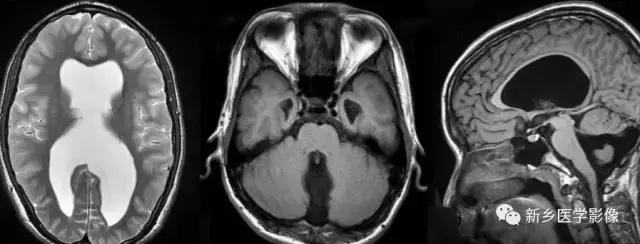

(3)无脑回和巨脑回

无脑回和巨脑回是一组因神经元移行异常所致的脑回发育异常。巨脑回也称平滑脑。巨脑回指有部分脑回存在,这些脑回异常增大增宽.脑沟变浅。巨脑回主要位于额、颞部。无脑回上要位于顶、枕部。

临床上,无脑回和巨脑回畸形患儿均表现有小头畸形和轻微的面部异常,完全无脑回畸形常在两岁前死亡.不完全无脑回畸形存活常能长期。

CT和MR均能够很好显示无脑回和巨脑回畸,表现为大脑半球表面几乎呈光滑状,仅可见少数宽阔、粗大、平坦的脑回,脑沟缺如.脑灰质增厚,脑白质变薄,灰白质分界面异常平滑,见不到白质向灰质内伸入的现象。常见透明中隔腔存在.侧脑室扩大,蛛网膜下腔增宽。